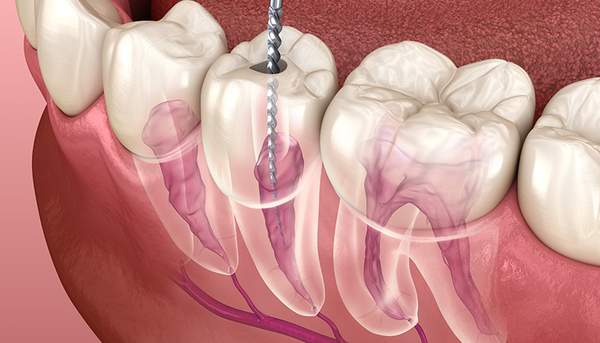

図のように、歯の神経は複雑で入り組んだ構造になっており、内部の膿や細菌を100%取り除くことは難しいのです。

そのなかでいかに細菌を消毒し、歯の神経の繊維を除去できるかが治療の要になるわけですが、そのために必要なのが歯を拡大してみることができる機材です。その一つがルーペです。ルーペにもよりますが、約2〜7倍拡大できます。